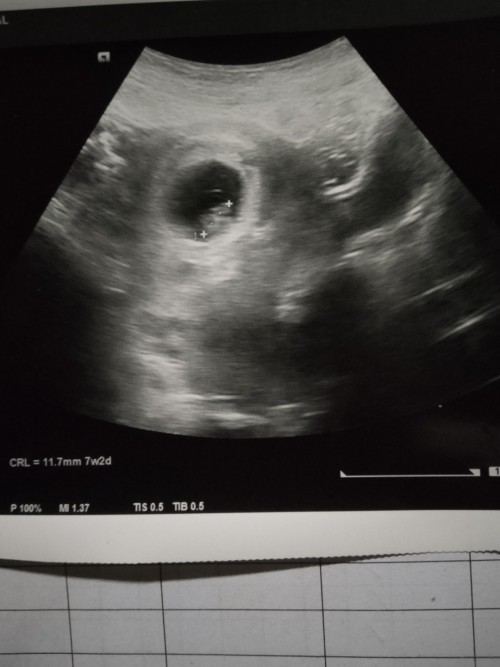

7วีคค่ะ

Post reply image